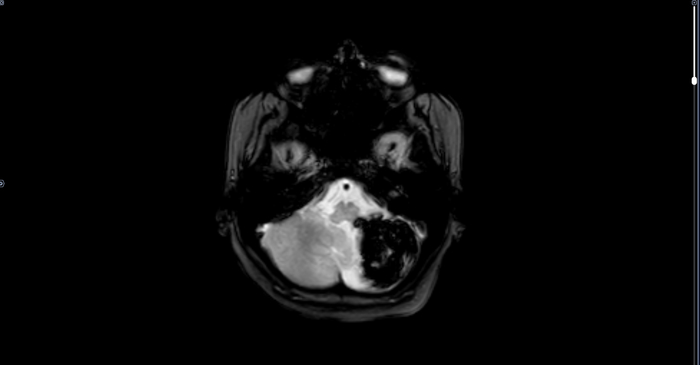

МРТ-Крупная кавернома мозжечка

Серия МРТ

МРТ головного мозга пациента с жалобами на сильную головную боль в затылке, нарушение координации.

В левой гемисфере мозжечка определяется участок патологического МР-сигнала неправильной формы, неоднородно гиперинтенсивный по Т2, Т1, FLAIR со снижением сигнала по периферии (на фоне отложения гемосидерина), гипоинтенсивный по DWI, SWI-восприимчивый, с нечеткими неровными контурами, размерами 3,2х4,1х3,6 см, с признаками перифокального отека. МР картина каверномы левой гемисферы мозжечка больших размеров, малых размеров правой лобной доли

Рек-но: конс. нейрохирурга, решение вопроса об оперативном лечении.

Категория годности по ст.23 а-Д(не годен к в/сл).